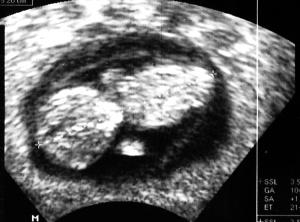

Hallo, jetzt habe ich es geschafft, das Bild von heute zu scannen. Es ist finde ich nicht so gut getroffen, aber man kann das Gummibärchen doch erkennen. Die Beine sind nicht zu sehen, waren im Schall aber da und haben sich auch schon deutlich bewegt :-) Die Ärmchen auch... Hach, es ist sooo schön! Ausserdem haben wir es doch heute schon dem großen Bruder gesagt. Wir haben zuerst mit ihm das Bilderalbum von seiner Schwangerschaft / erste Babytage angeschaut und da ist auch ein Ultraschallbild von ihm drin in der gleichen Woche. Dann sagte mein Freund: "Ich hab noch ein Bild..." und holte das Bild vom Bauchzwerg raus. Und ich meinte: "Und das ist in mir drin." Zuerst war mein Sohn völlig verwirrt und hats überhaupt nicht kapiert, aber dann klickerte es und als ich sagte: "Du wirst großer Bruder. Du bekommst ein Geschwisterchen." war er völlig aus dem Häuschen. Er war plötzlich total von den Socken, hüpfte ganz aufgeregt herum und freute sich ganz offensichtlich total! :-))) Er fragte dann, wie lange es noch dauert und dass er es kaum erwarten könne und dass ja dann mein Bauch wieder dick wird und er die Tritte spüren kann usw usw... Später sagte ich zu ihm, dass ich mich freue, dass er sich freut und er sagte: "Ja. Endlich bekomme ich ein Geschwisterchen. Das hatte ich echt nicht mehr erwartet." Ich hatte ja Sorge, wie er reagieren würde - er ist ja schon 8, hatte nie einen Geschwisterwunsch, im Gegenteil, wenn ich gefragt habe, wollte er immer lieber keine. Und wenns sein muss, dann einen Bruder. Und jetzt freut er sich total und meinte, er hoffe, es wird ein Mädchen! 8-) So, also heute war auf der ganzen Linie ein schöner Tag! Erst prima Ultraschall, dann prima Reaktion des großen Bruders. Was will man mehr? Gruß, Julia

Och da hab ich gleich Tränen in den Augen!!!! Schön, dass er so begeistert war und sich freut! Wir sagen es unserem Sohn am Samstag in aller Ruhe, denn am Sonntag wird er 4 Jahre alt und da ist dann die gesamte Familie da und dann wollen wir es allen sagen. Bin auch schon total auf seine Reaktion gespannt! Übrigens sieht euer Krümel gar nicht mehr krümelig aus - richtig groß schon, wow!!!